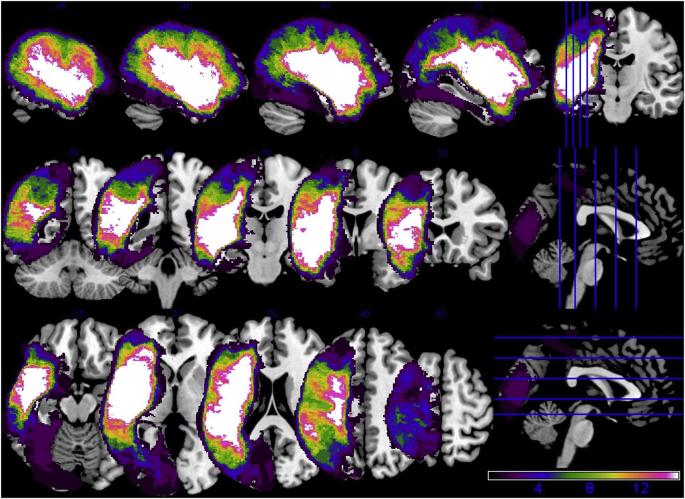

Traditional models of left hemisphere stroke recovery propose that reactivation of remaining ipsilesional tissue is optimal for language processing whereas reliance on contralesional right hemisphere homologues is less beneficial or possibly maladaptive in the chronic recovery stage. However, neuroimaging evidence for this proposal is mixed. This study aimed to elucidate patterns of effective connectivity in patients with chronic aphasia in light of healthy control connectivity patterns and in relation to damaged tissue within left hemisphere regions of interest and according to performance on a semantic decision task. Using fMRI and dynamic causal modeling, biologically-plausible models within four model families were created to correspond to potential neural recovery patterns, including Family A: Left-lateralized connectivity (i.e., no/minimal damage), Family B: Bilateral anterior-weighted connectivity (i.e., posterior damage), Family C: Bilateral posterior-weighted connectivity (i.e., anterior damage) and Family D: Right-lateralized connectivity (i.e., extensive damage). Controls exhibited a strong preference for left-lateralized network models (Family A) whereas patients demonstrated a split preference for Families A and C. At the level of connections, controls exhibited stronger left intrahemispheric task-modulated connections than did patients. Within the patient group, damage to left superior frontal structures resulted in greater right intrahemispheric connectivity whereas damage to left ventral structures resulted in heightened modulation of left frontal regions. Lesion metrics best predicted accuracy on the fMRI task and aphasia severity whereas left intrahemispheric connectivity predicted fMRI task reaction times. These results are discussed within the context of the hierarchical recovery model of chronic aphasia.

传统的左半球卒中恢复模型提出,剩余同侧组织的再激活对于语言处理是最佳的,而依赖对侧右半球同功是在慢性恢复阶段不太有益或可能适应不良的。然而,对于这一建议的神经影像学证据是混杂的。本研究旨在阐明慢性失语症患者的有效连接模式,根据健康对照组的连接模式,并根据左半球感兴趣区域内受损组织和语义决策任务的表现,阐明有效连接模式。使用 fMRI 和动态因果建模,在四个模型家族中创建了符合潜在神经恢复模式的生物合理模型,包括家族 A:左侧连接(即,无/最小损伤)、家族 B:双侧前加权连接(即,后损伤)、家族 C:双侧后加权连接(即,前损伤)和家族 D:右侧连接(即,广泛损伤)。对照组表现出对左侧网络模型(家族 A)的强烈偏好,而患者则表现出对家族 A 和 C 的偏好。在连接水平上,对照组表现出比患者更强的左侧半球内任务调节连接。在患者组中,左侧额上结构的损伤导致右侧半球内连接增强,而左侧腹侧结构的损伤导致左侧额叶区域的调节增强。损伤指标最好预测 fMRI 任务和失语症严重程度的准确性,而左侧半球内连接预测 fMRI 任务反应时间。这些结果在慢性失语症的层次恢复模型的背景下进行了讨论。